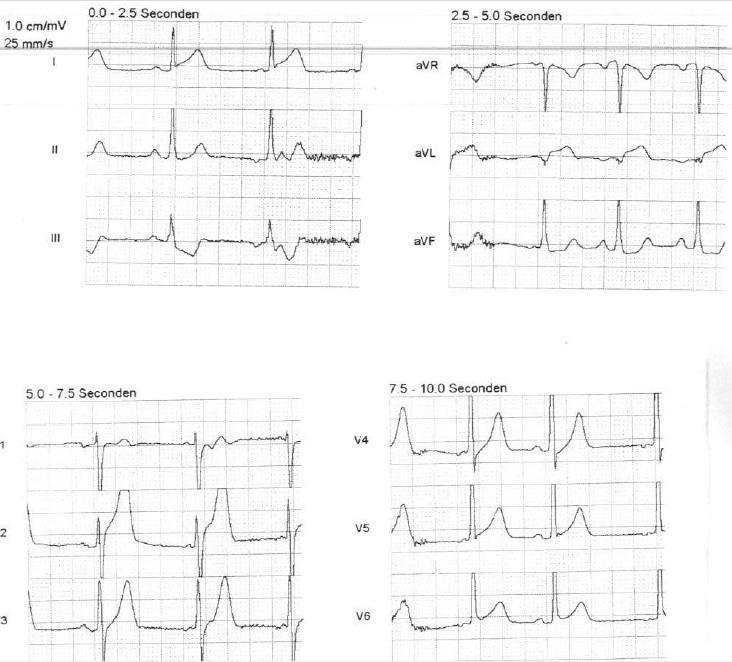

Figuur 1 – Elektrocardiogram van de ambulance dienst

Op het elektrocardiogram (figuur 1) ziet u een sinusritme. De stand van de elektrische hartas is normaal. De PQ-tijd meet 160 msec, de QRS-duur 100 msec. De QT-tijd 400 msec. De repolarisatie is abnormaal met ST-segment elevaties in afleidingen I, aVL en V6. Reciproke ST-segment depressies in afleidingen III en aVF. Het ECG past bij een anterolateraal myocardinfarct.